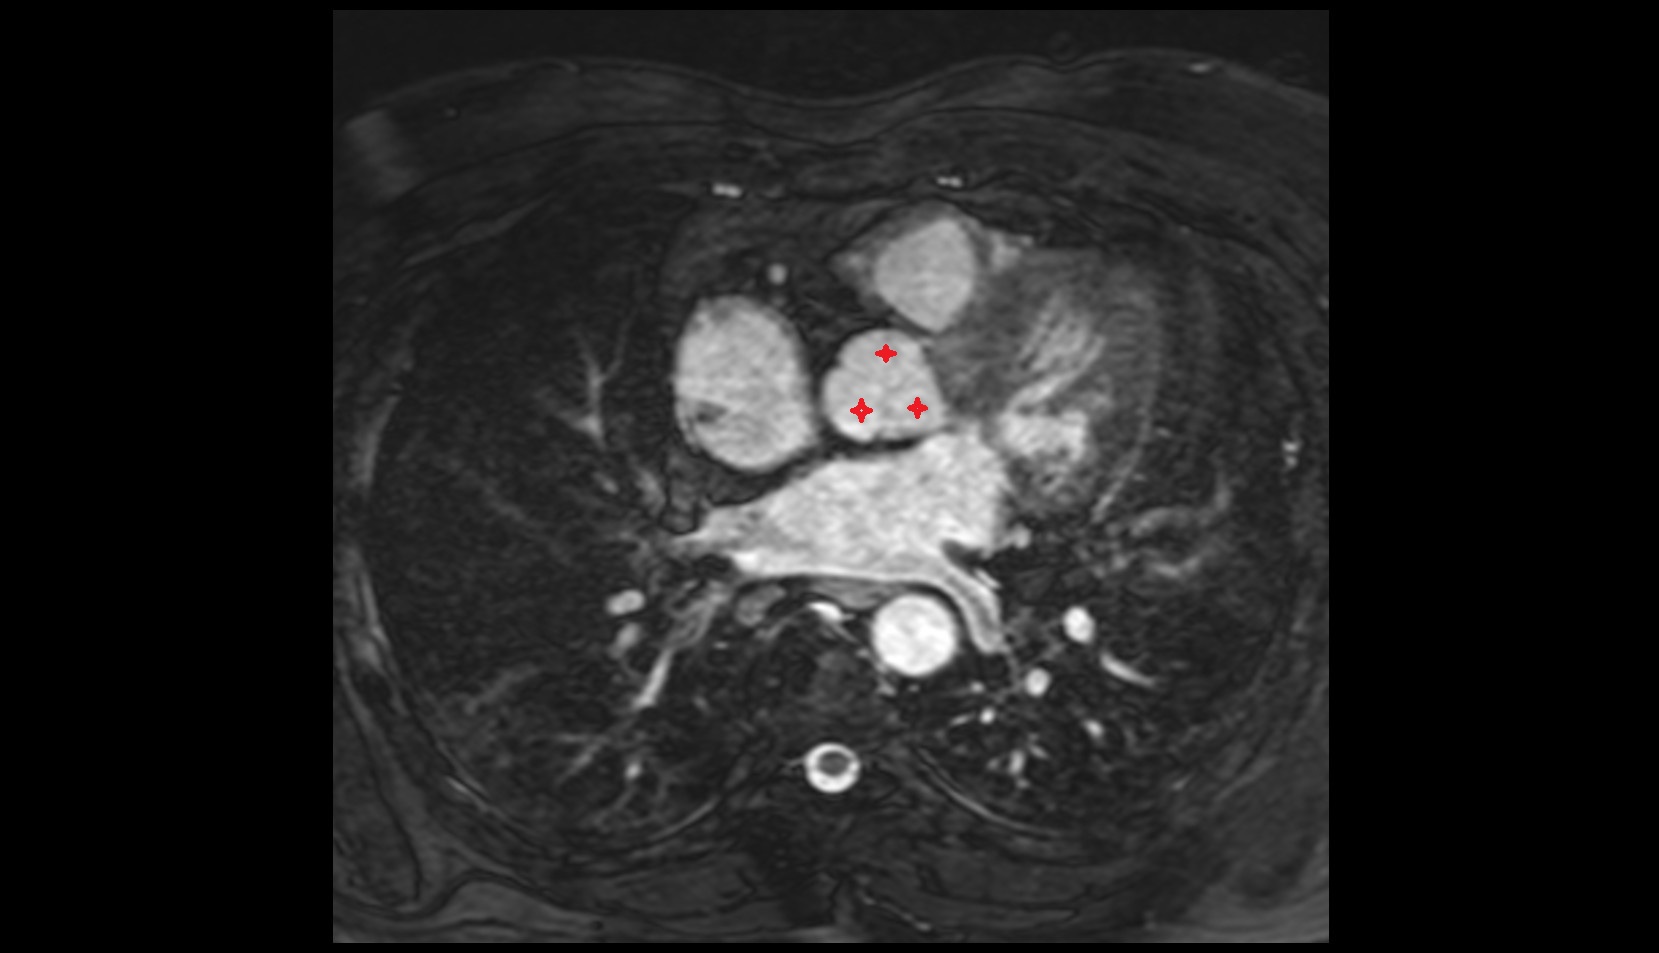

- Left atrioventricular valve (mitral or bicuspid valve)

- Right atrioventricular valve (tricuspid valve)

- Pulmonary valve

- Interventricular Septum